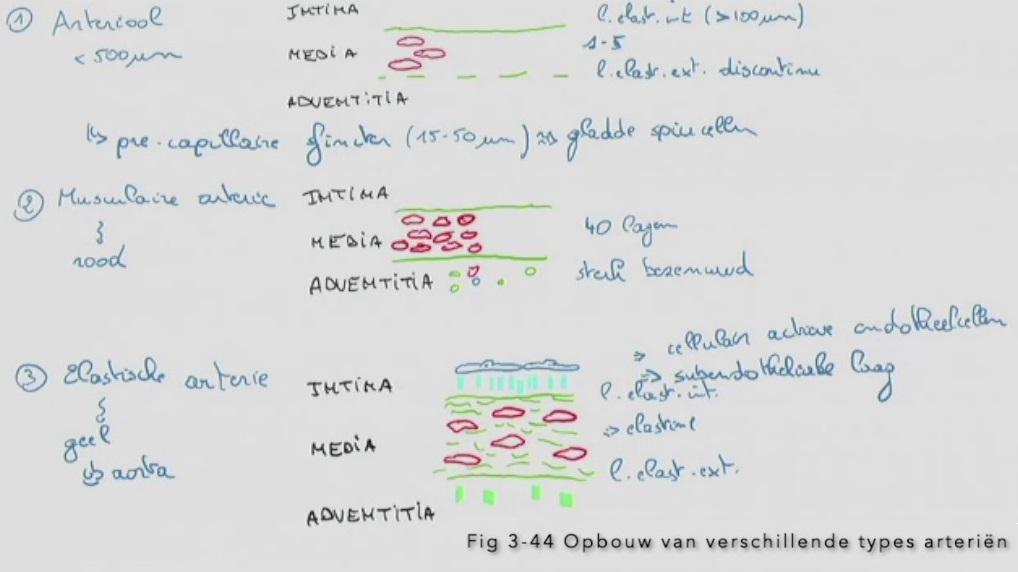

Fig 3.44: Opbouw van verschillende types arterien

A arteriool (< 500 um)

B musculaire arterie (rode kleur)

C elastische arterie (gele kleur, bv. aorta)

-

tunica intima

lamina elastica interna -

tunica media

gladde spiercellen elastinevezels

lamina elastica externa -

tunica adventitia

|